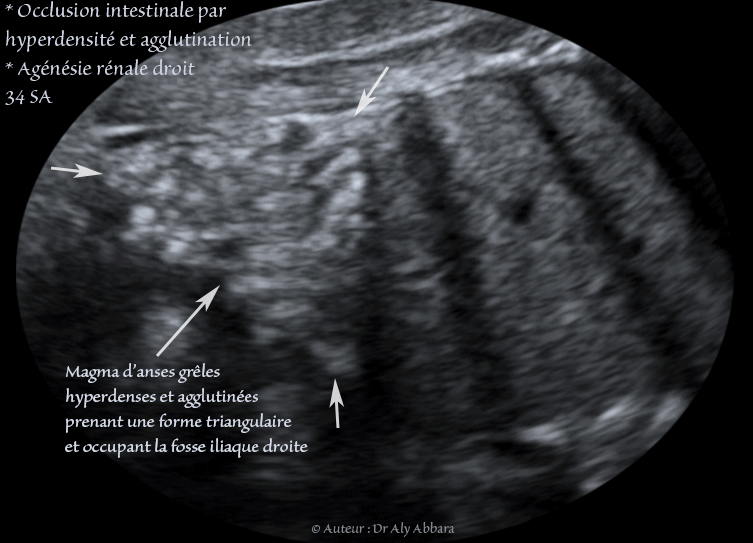

Cette occlusion intestinale est liée à la présence, dans la fosse iliaque droite, comme on le voit sur ces images, d'un magma d'anses grêles hyperdenses, agglutinées et obstruées.

Ce magma digestif intestinal prend une forme triangulaire (pyramidale) sur la coupe frontale de l'abdomen centrée sur la fosse iliaque droite

Il s'agit d'une fœtus de 34 SA ; après sa naissance à 38 SA, cette occlusion des anses grêles a nécessité deux interventions chirurgicales digestives dans la période néonatale.